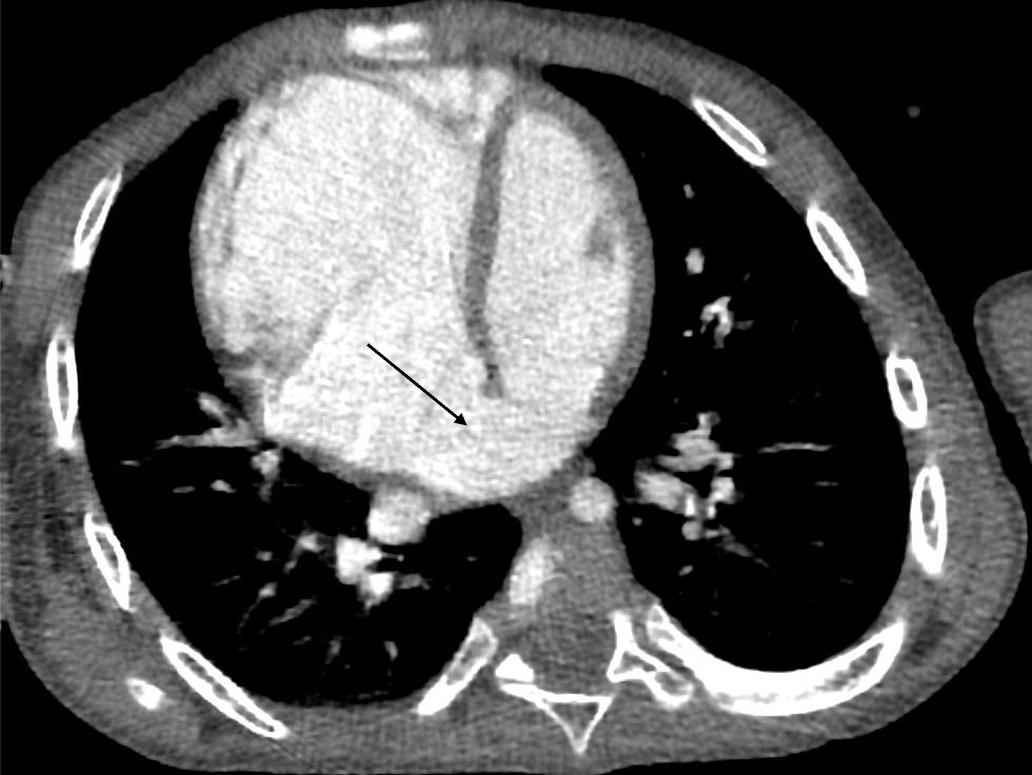

3歳、 男児、 9kg、 心房中隔欠損

染色体異常が判明している男児。肺炎で入院した際のレントゲンで右心系の拡大を指摘された。心臓超音波検査にて心房間の短絡が疑われた。心房中隔欠損症疑いの精査、肺静脈還流異常の除外目的で造影CT検査が施行された。

心房中隔欠損症は左右の心房に短絡を生じる先天性の病態である。欠損部位により、二次孔欠損、一次孔欠損および冠静脈洞欠損に大別される。まず身体所見、胸部レントゲン写真および心電図検査が行われ、解剖学的構造を評価するために、心エコー検査が施行される。心エコー検査で十分な情報が得られない場合、欠損孔の部位や形態を評価するために造影CTが施行される。最終的な治療方針の決定にはカテーテル検査が施行されることが多いが、あらかじめ病変の形態や解剖を把握するために造影CTは有用である。また肺静脈還流異常を合併することがあるため、その有無を評価することができる。短絡が小さいものについては経過観察が可能であるが、ある程度大きい病変に対しては治療が必要となる。治療はカテーテルによる閉鎖術、外科手術が挙げられる。カテーテルによる閉鎖術が選択される場合には、造影CTは治療計画用にも用いられる。その場合には、任意多断面再構成(MPR)やvolume rendering(VR)像などを活用する。